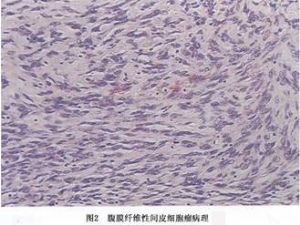

(1)纤维性间皮瘤:纤维性间皮瘤瘤细胞由梭形细胞组成,细胞呈长梭形,伴有多少不等的胶原纤维,这种类型多见于局限性间皮瘤。在纤维性间皮瘤有时很难与纤维组织肿瘤相区别,瘤细胞呈梭形,细胞周围可有胶原化,甚至可有编织状结构,局灶性钙化或骨化,当间质有明显的纤维化或玻璃样变时,有人称它为韧带样间皮瘤。最近亦有人将来自间皮下的结缔组织来源的肿瘤称为腹膜纤维瘤。来自表层间皮细胞的才称纤维性间皮瘤。但单纯根据组织形态,有时难以将两者区别开来(图2)。

(1)纤维性间皮瘤:纤维性间皮瘤瘤细胞由梭形细胞组成,细胞呈长梭形,伴有多少不等的胶原纤维,这种类型多见于局限性间皮瘤。在纤维性间皮瘤有时很难与纤维组织肿瘤相区别,瘤细胞呈梭形,细胞周围可有胶原化,甚至可有编织状结构,局灶性钙化或骨化,当间质有明显的纤维化或玻璃样变时,有人称它为韧带样间皮瘤。最近亦有人将来自间皮下的结缔组织来源的肿瘤称为腹膜纤维瘤。来自表层间皮细胞的才称纤维性间皮瘤。但单纯根据组织形态,有时难以将两者区别开来(图2)。